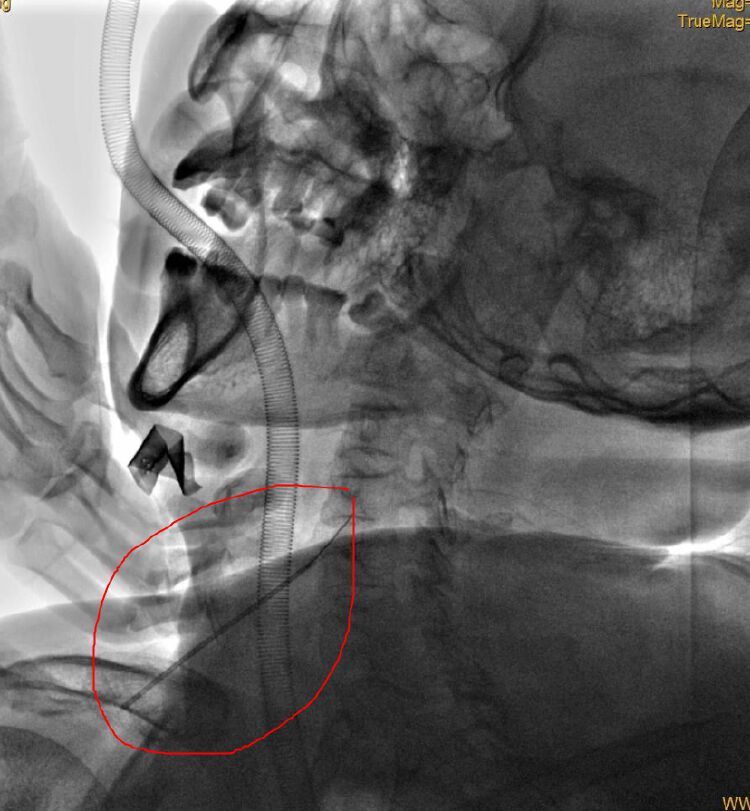

在DSA室里,在射线的透视下,胸外科张建华主任团队寻找着金属异物的位置——在食管和脊柱之间的间隙里。此时,胸外科还想努力一下,用微创的方法取出来。但异物的两头尖锐、光滑,医生尝试用穿刺针都套不住,因为它是不规则形状,两头尖,中间还有螺纹,胸外科医生们好不容易用穿刺针把它套住了,往外一拽,又掉了!

屡次尝试无果,医生无奈选择开刀。胸外科医生在张先生的颈部右侧开了一个口子,大约3公分,手指伸进去,感受到异物的位置,然后慢慢把它推回食管内。

这下,异物在胃镜下终于暴露无遗了,完全360度无死角,轮到消化内科医生上场了,医生一拽,就把异物拉出来,真的是一根金属针,足足有2.5厘米那么长。困扰着张先生的“如鲠在喉”终于被解除!近日已恢复正常饮食,准备出院。